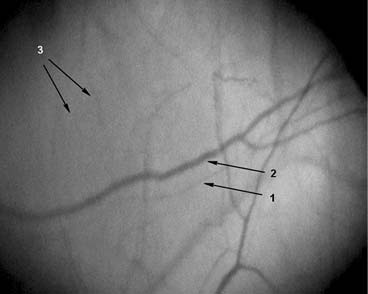

Для иллюстрации материалов на рис. 1–3 представляем фрагменты МЦР бульбарной конъюнктивы некурящего, курящего и прекратившего курить пациентов с АГ.

Рис. 3. Фрагмент микроциркуляторного русла конъюнктивы. Увеличение ×96. Пациент Т. 40 лет, курил 23 года по 20 сигарет в день, не курит 1,3 года. Страдает артериальной гипертензией 2-й степени, риск 3, в течение 7 лет. Артериальное давление на момент исследования 132/78 мм рт.ст., пульс 61 в минуту. 1 — артериола (d=21,8 мкм); 2 — венула (d=30,6 мкм), артериоло-венулярный коэффициент 0,71; 3 — капилляры (d=8,8 мкм), количество капилляров на 1 мм2 поверхности конъюнктивы 6,12 ед./мм2